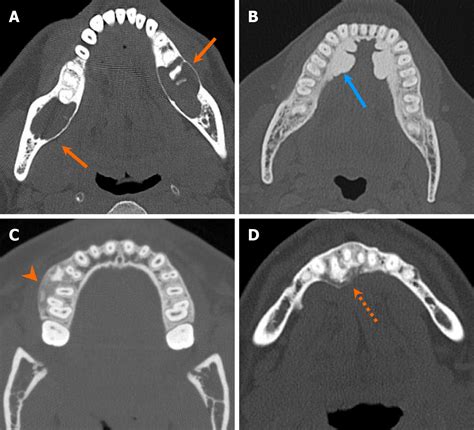

The diagnosis of a cancerous jaw tumor typically involves a combination of clinical examination, imaging studies, and biopsy. The diagnostic process may include:

• Clinical examination: A healthcare professional will examine the jaw and surrounding areas for any signs of swelling, tenderness, or abnormalities.

• Imaging studies: X-rays, CT scans, MRI, or PET scans may be used to visualize the tumor and determine its extent.

• Biopsy: A small sample of the tumor tissue is removed and examined under a microscope to confirm the presence of cancer cells.

In some cases, additional tests may be required to determine the stage of the cancer and whether it has spread to other parts of the body.